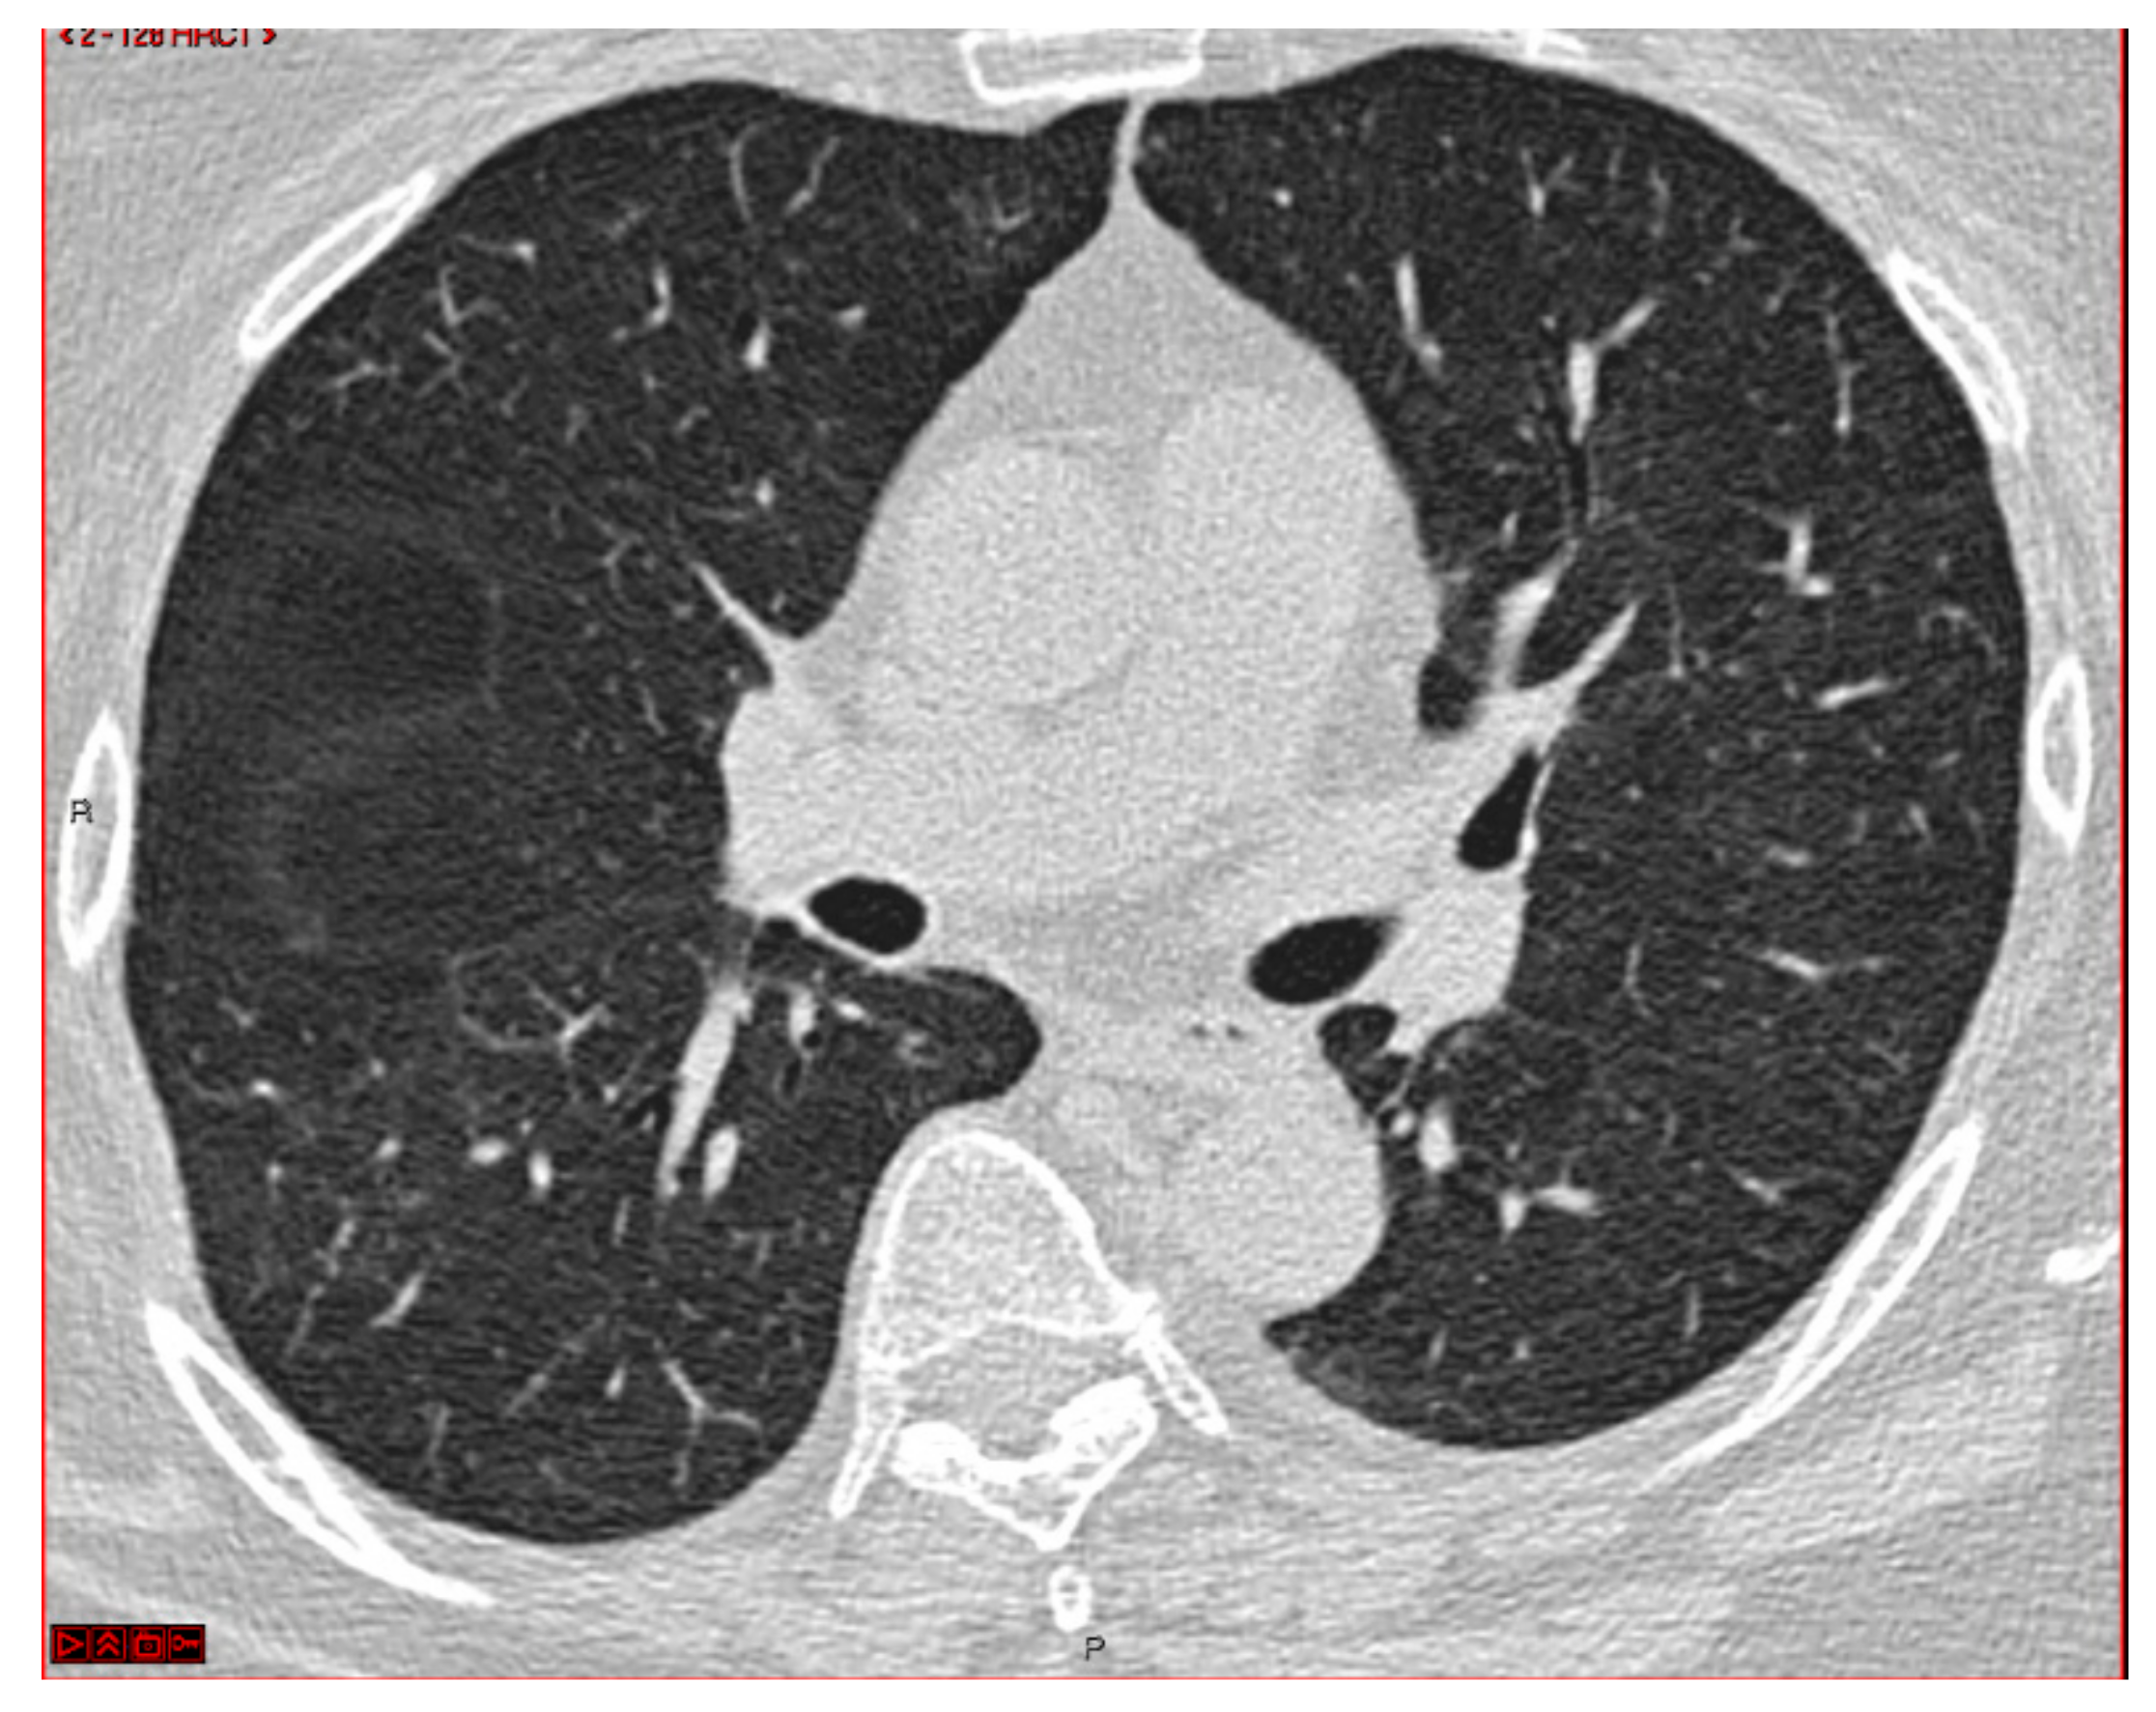

2. Case Presentation